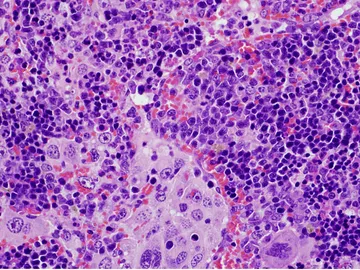

Descubren una nueva terapia contra el gioblastoma

Un reciente descubrimiento revela que una infección grave por COVID-19 puede reducir el tamaño de los tumores

Este fármaco sería efectivo contra los tumores cerebrales